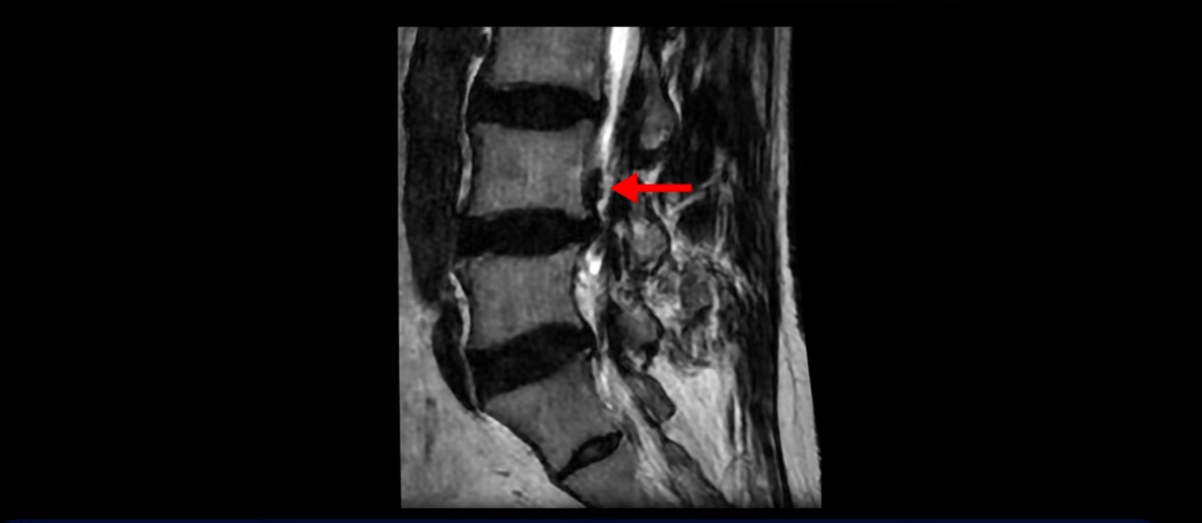

이분 MRI를 보면 허리 세 마디 정도의 퇴행성 디스크가 있고

하지만 이분의 갑작스러운 통증을 일으키는 원인은 4번 5번에 발생한 디스크 파열입니다.

이분은 왼쪽 무릎 아래로 본인 표현으로는 다리를 잘라 버리고 싶다고 할 정도의 심한 통증이 있는데 보통 이런 표현은 디스크 파열이 발생했을 때 많이 사용하는 표현입니다. 이분 4번 5번 디스크를 자세히 보면 왼쪽으로 파열되어 밀려 올라간 디스크 수핵을 볼 수 있습니다.